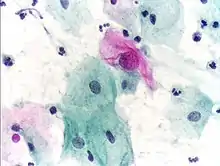

Micrograph of a Pap test showing a low-grade intraepithelial lesion (LSIL) and benign endocervical mucosa. Pap stain.